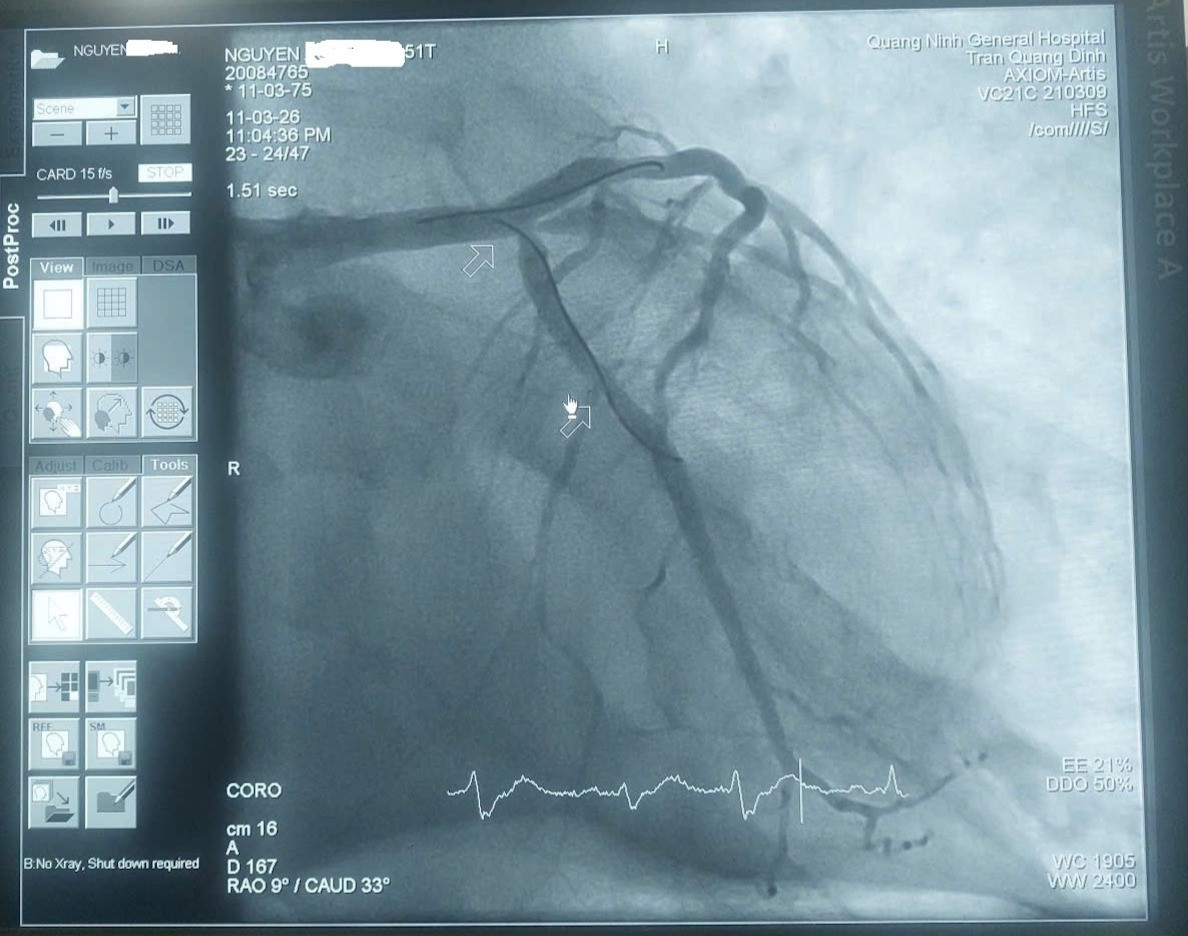

Hình ảnh mạch vành của bệnh nhân được tái thông sau can thiệp kịp thời. Ảnh: BVCC

Kết quả chụp mạch vành cho thấy hẹp khít thân chung động mạch vành trái. Ê-kíp đã đặt một stent đoạn LM–LAD, các nhánh còn lại hẹp mức độ vừa và được điều trị nội khoa.